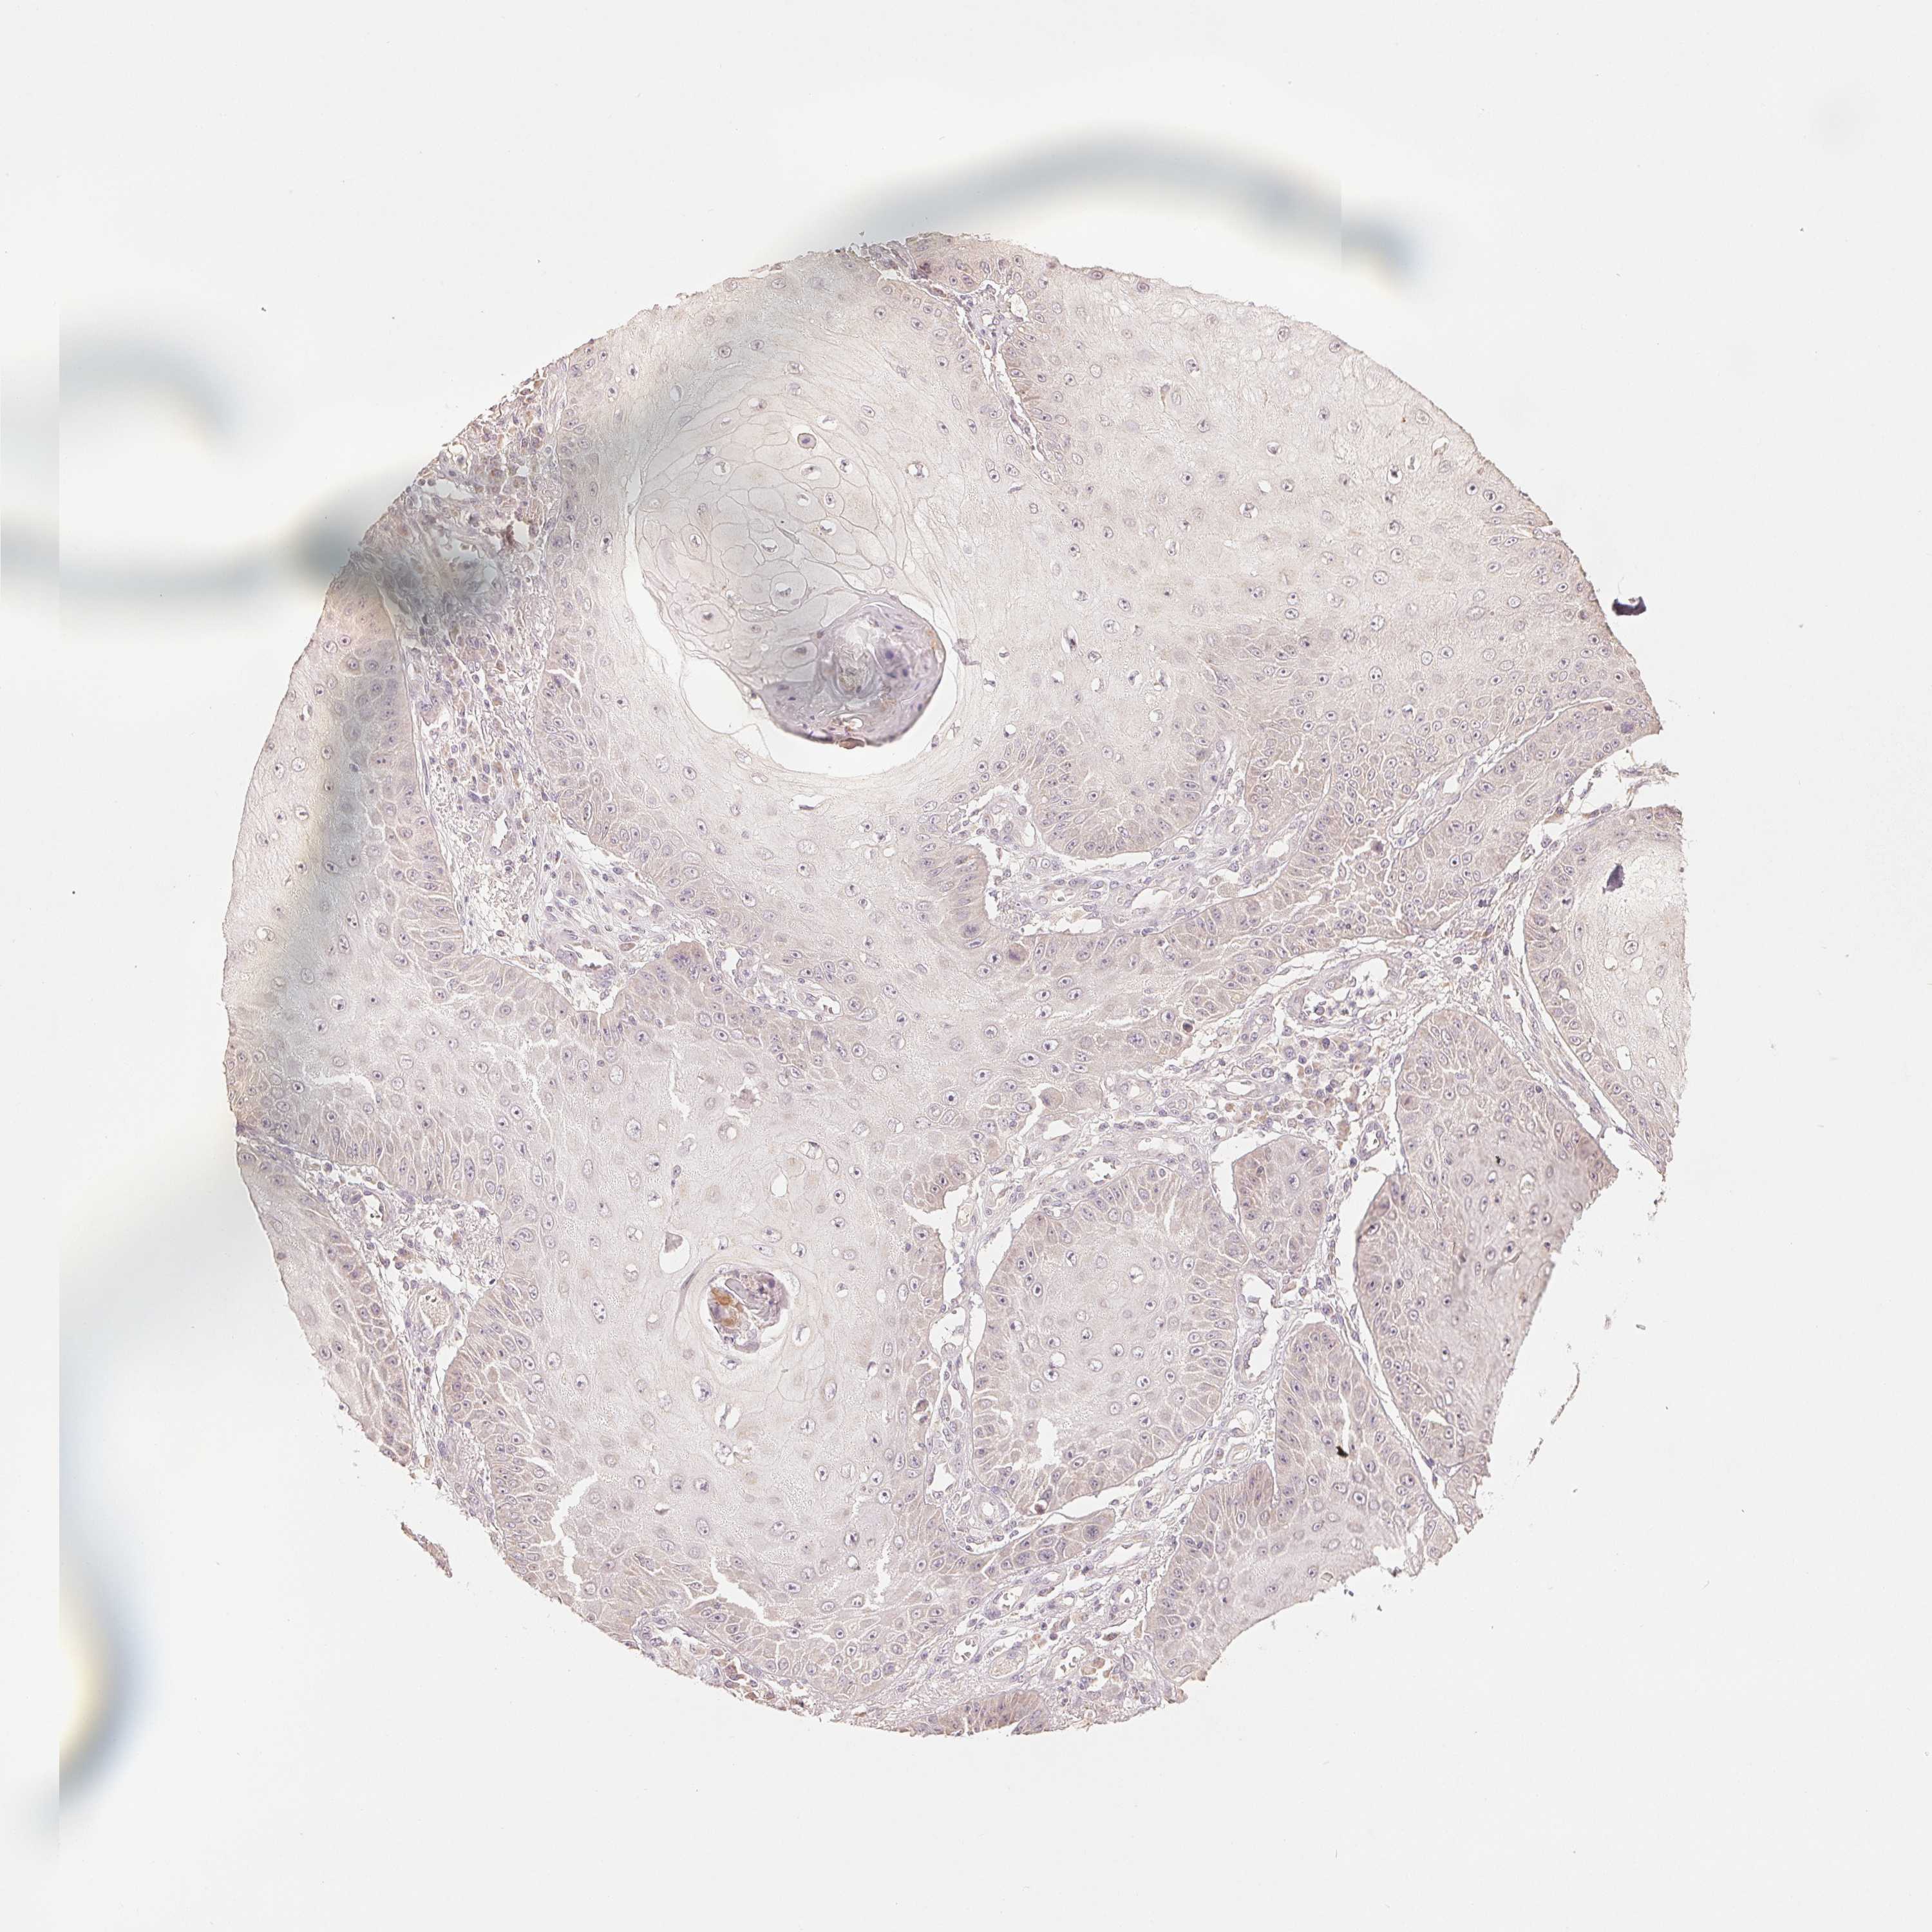

SKIN CANCER - Protein expressioni

A mouse-over function shows sample information and annotation data. Click on an image to view it in a full screen mode. Samples can be filtered based on level of antibody staining by selecting one or several of the following categories: high, medium, low and not detected. The assay and annotation is described here.

Antibody stainingi

Antibody staining in the annotated cell types in the current human tissue is reported as not detected, low, medium, or high, based on conventional immunohistochemistry profiling in selected tissues. This score is based on the combination of the staining intensity and fraction of stained cells.

Each image is clickable and will lead to virtual microscopy that enables deeper exploration of all samples and also displays staining intensity scores, fraction scores and subcellular localization as well as patient and tissue information for each sample.

Antibody HPA044618

Antibody HPA062014

Basal cell carcinoma

Squamous cell carcinoma, NOS

Squamous cell carcinoma, metastatic, NOS

BCC, high aggressive